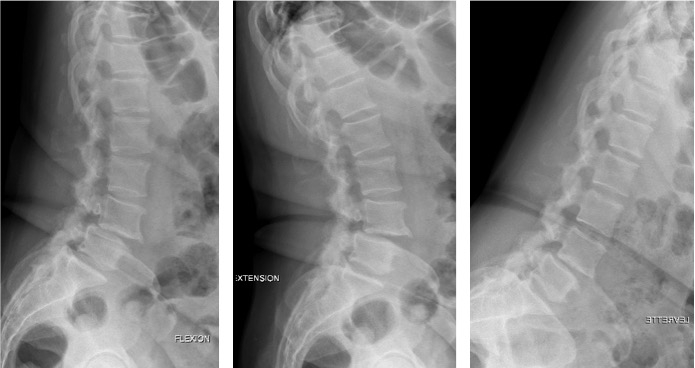

Des radiographies standard sont nécessaires pour évaluer la morphologie globale de la colonne (Figure 3). Le caractère mobile du spondylolisthésis est évalué sur des clichés dynamiques de face en inclinaison latérale (bendings) et de profil (en flexion, extension et en chien de fusil).

Figure 3. Bilan préopératoire d'une scoliose lombaire dégénérative avec discopathie frontale L4-L5 en vue d'une arthrodèse lombaire intersomatique par voie antérolatérale instrumentée par cage.